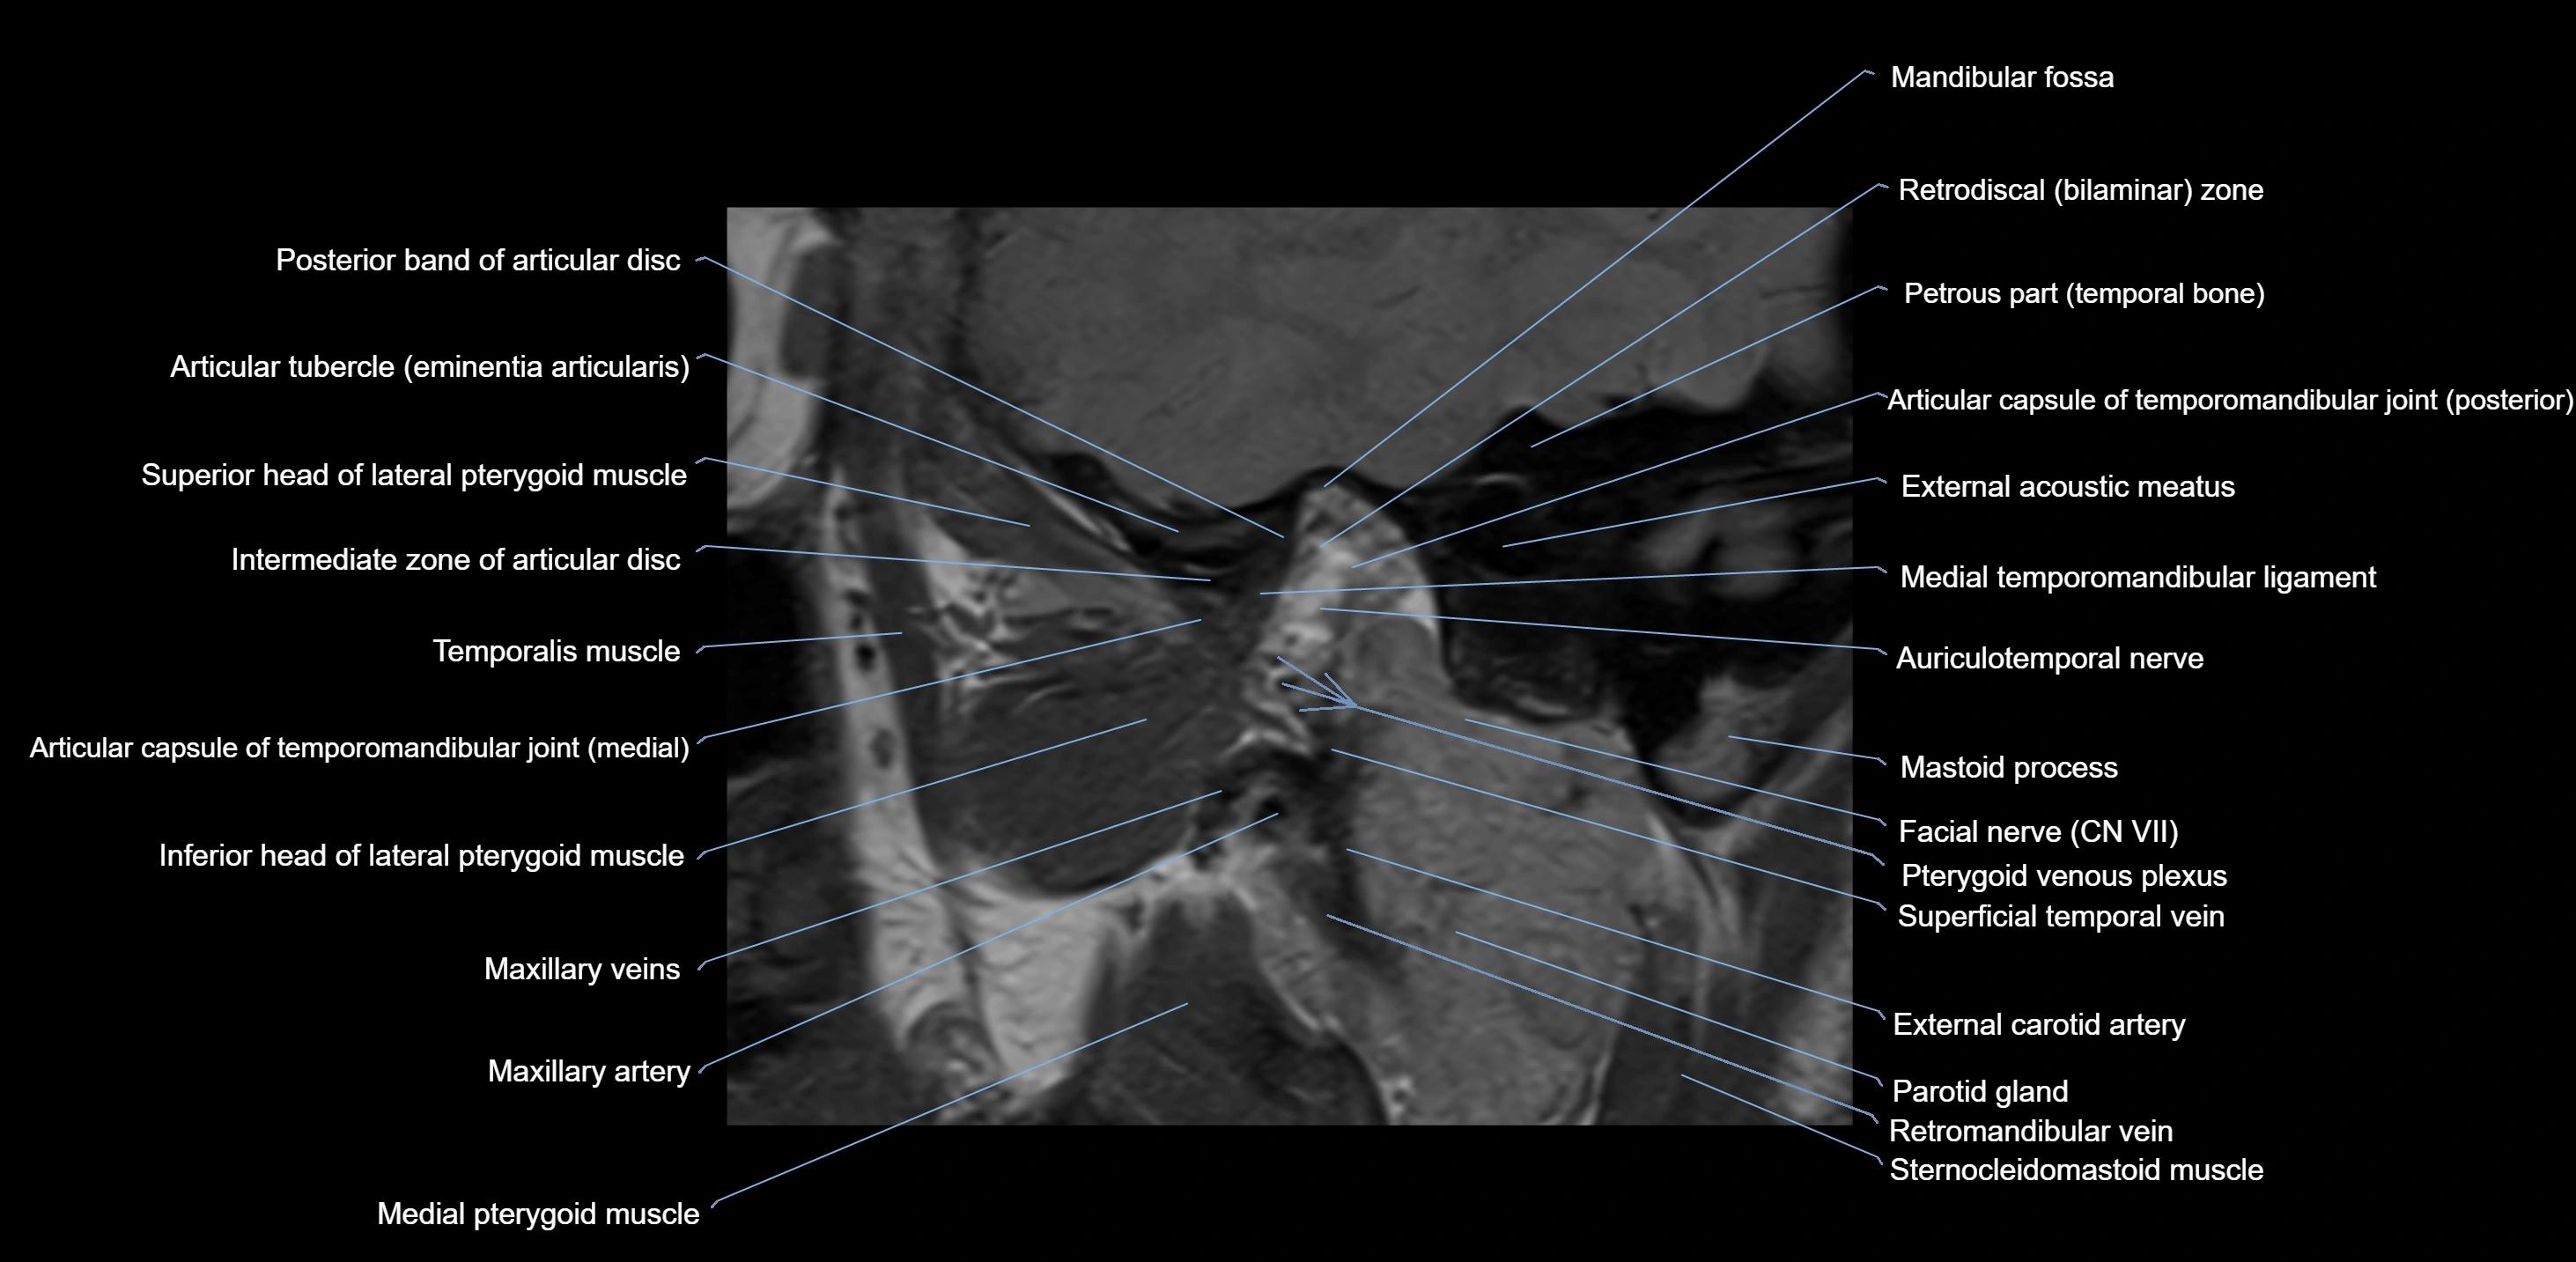

MRI appearance

T1-weighted images:

• Cortical bone: Low signal intensity

• Cancellous marrow: Intermediate to high signal depending on fatty content

• Teeth: Signal void structures

• Adjacent soft tissues: Normal gingiva and oral mucosa signal

T2-weighted images:

• Cortical bone and teeth: Low signal

• Marrow: Intermediate signal